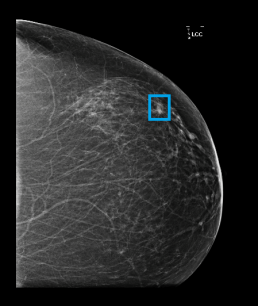

A spiculated mass of 1.5 cm diameter and an associated distorsion are detected in the upper outer left breast, situated 7-8 cm from the nipple.

When looking retrospectively at this case, this spiculated mass was already present 6 years before. On the 2014 mammogram, MammoScreen gave a score of 8, highest suspicion, alerting on the potential malignancy of this lesion.